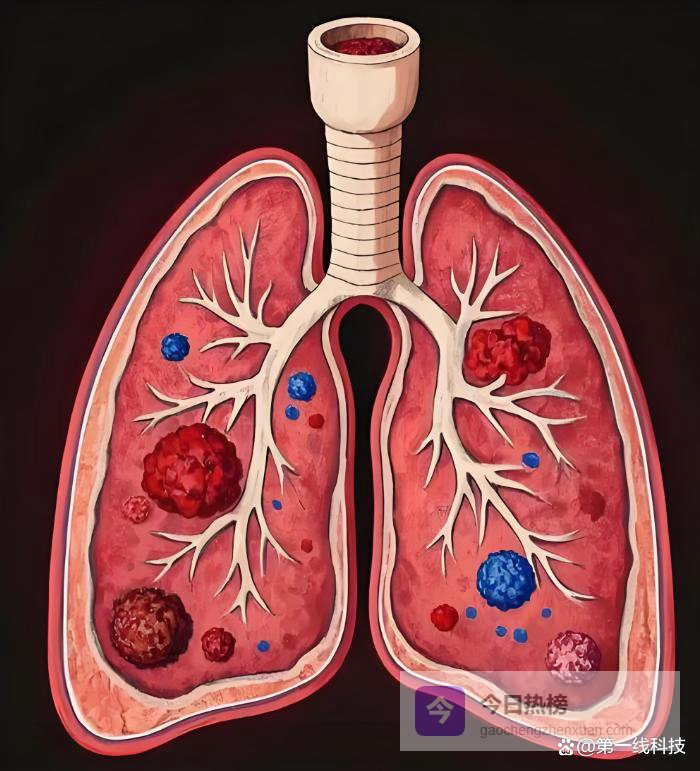

2026年2月发表在《自然》杂志上的一项研究,肺腺癌,这种最常见的肺癌,能像黑客一样入侵你的神经系统。 它通过迷走神经,给你的大脑发送错误指令,让大脑命令身体“保护”肿瘤,反过来打压你自己的免疫系统。 这不是科幻电影,这是正在发生的癌症战争新前线。

宾夕法尼亚大学和耶鲁大学的团队,在一种特定基因突变(KrasG12D和Trp53缺失)导致的肺腺癌小鼠身上,看到了惊人的一幕。 在高清三维成像下,肺里的肿瘤根本不是孤岛。 它的内部和周围,被密密麻麻的神经纤维穿透、缠绕,像被电网覆盖一样。 这些神经的密度,比旁边健康的肺组织要高得多。

起初,研究者以为这条神经是在搞“局部破坏”。 他们发现,这些神经的存在,会让肿瘤里的肺泡巨噬细胞(一种免疫细胞)变成“维稳派”,失去攻击性,转而抑制冲锋陷阵的T细胞功能,营造一种对癌细胞友好的“免疫抑制”环境。 但奇怪的是,这条神经末梢释放的主要信号物质,却跟免疫调控无关。

锁被打开,巨噬细胞的属性发生了根本转变。 它从潜在的抗肿瘤战士,变成了坚定不移的“保护伞”。 它的表面特征变化,分泌的因子也变化,全力抑制CD8+ T细胞等能杀死癌细胞的免疫主力军。 至此,一个可怕的、完整的恶性循环形成了:肺癌招募神经,神经向大脑发送假情报,大脑被欺骗后发出加强版错误指令,指令促使神经释放更多抑制信号,最终完美地压制了免疫系统。 肿瘤就这样,在大脑的“帮助”下,安全地茁壮成长。